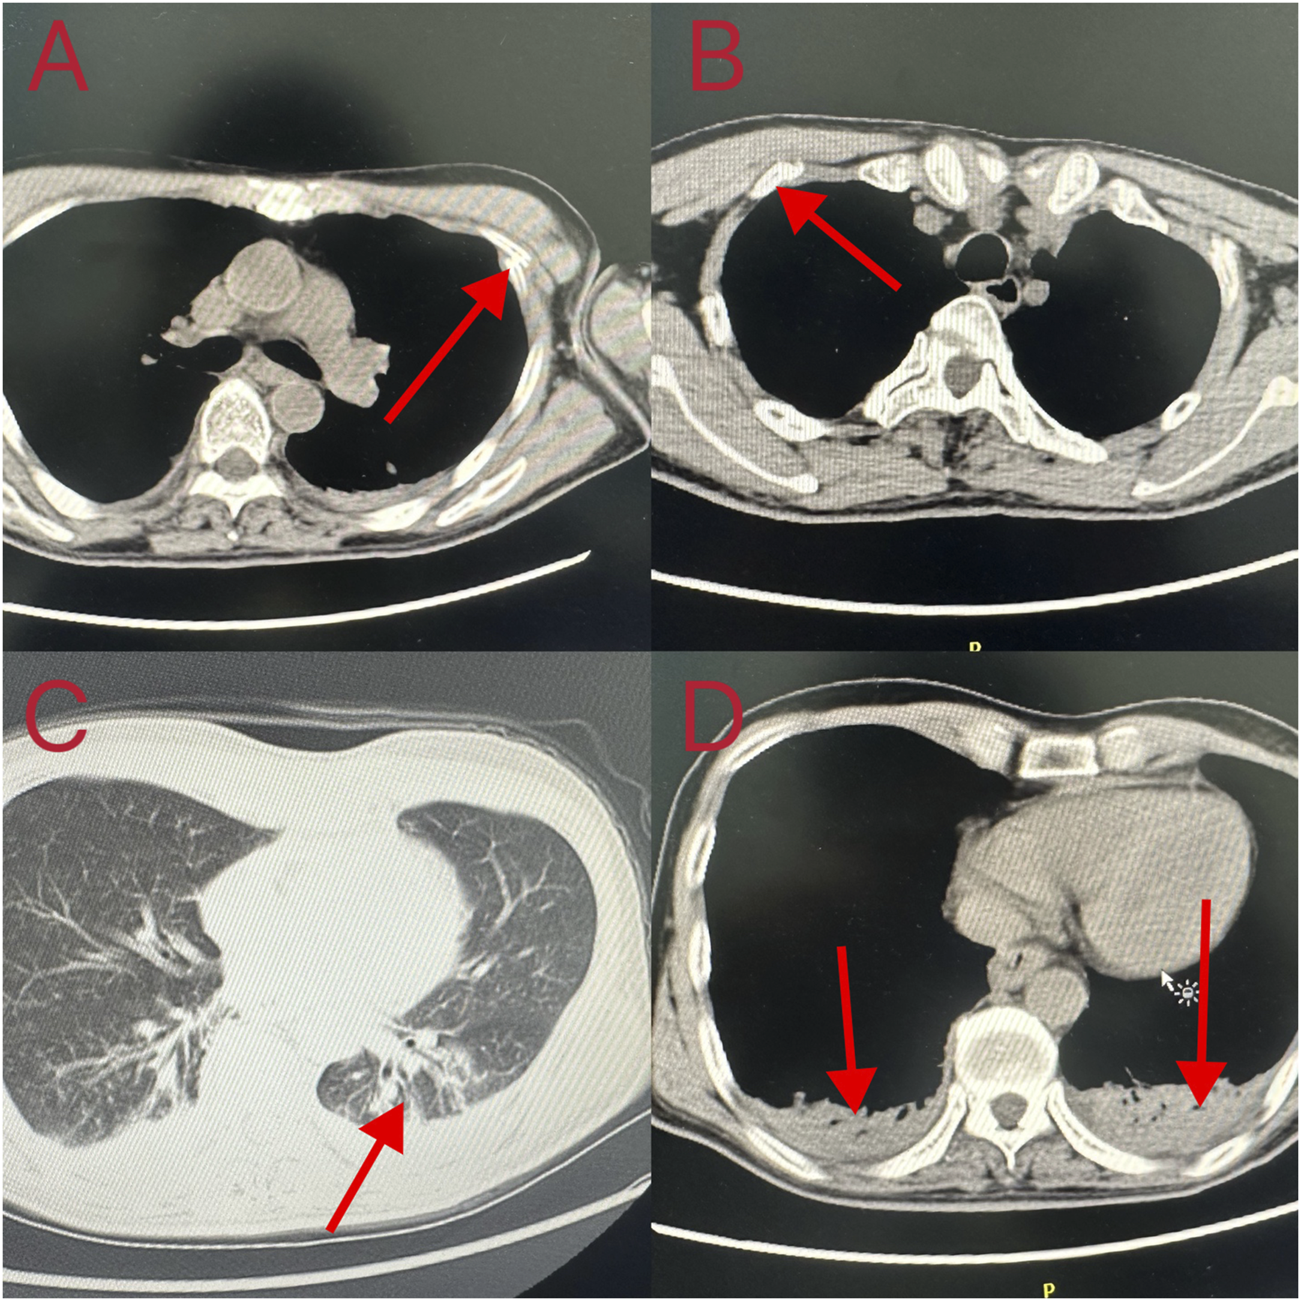

Cardiopulmonary resuscitation, oxygen inhalation, infusion, and other related treatments were urgently performed, and the patient was first sent to a local hospital for treatment. After admission, symptomatic treatments such as anti-infection, free radical scavenging, asthma relief, myocardial protection, anti-epilepsy, stomach protection, and fluid infusion were administered. After 2 days of hospitalization, he was transferred to our hospital for further diagnosis and treatment on the early morning of 18 October 2023. Physical examination on admission revealed a body temperature of 37.1°C, pulse rate of 92 beats/min, respiratory rate of 20 breaths/min, and blood pressure of 100/86 mmHg. He was intubated and placed on ventilator-assisted ventilation and was in a coma. The pupils were 4 mm in diameter and unresponsive to light. Bilateral breath sounds were coarse and no dry or wet rales were heard. The rhythm was normal and no pathological murmur was heard in any valve area. The abdomen was flat and soft, and the liver and spleen under the ribs were not palpable. Physiological reflex was absent and a pathological reflex was not elicited. Electrocardiogram examination at admission revealed the following: sinus rhythm, abnormal lower wall ST-T, possibly due to myocardial ischemia. Auxiliary test results were as follows: blood gas analysis: arterial partial pressure of oxygen 201.5 mmHg; arterial partial pressure of carbon dioxide 49.3 mmHg; white blood cell count 16.23 × 109/L (3.5–9.5 × 109/L), neutrophil ratio 89% (40%–75%); and platelet count 121 × 109/L (125–350 × 109/L). Laboratory blood test results were as follows: alanine aminotransferase 48 U/L (9–50 U/L), aspartate aminotransferase 60 U/L (15–40 U/L), serum myoglobin 114 ng/mL (0–70 ng/mL), creatine kinase isoenzyme 7.10 ng/mL (0.3–4 ng/mL), serum high-sensitivity troponin I 170.85 (<17.5 ng/L), N-terminal pro-brain natriuretic peptide 1,387 pg/mL (emergency ≤300 pg/mL), interleukin-6 63.50 pg/mL (0–7 pg/mL), and interleukin-1b 6.15 pg/mL (0–5 pg/mL). Brain CT and magnetic resonance imaging showed no apparent abnormalities. Chest CT revealed double pneumonia, bilateral pleural effusion, multiple fractures of the left 1st to 6th ribs, fractures of the right 2nd and 3rd ribs, severe respiratory artifacts (Figure 2), and left pneumothorax (Figure 3). The admission diagnoses were acute dichloromethane poisoning, hemopneumothorax, and rib fracture. After admission, the patient was actively treated with anti-infection therapy, reduce organ edema, glucocorticoids, ventilator-assisted respiration, chest strap fixation, and nutritional support. On the 7th day after admission, the patient’s blood test results revealed a decrease in white blood cell count 11.37 × 109/L (3.5–9.5 × 109/L) and neutrophil ratio 80.1% (40%–75%), and increased levels of alanine aminotransferase 206 U/L (9–50 U/L) and aspartate aminotransferase 84 U/L (15–40 U/L). On the 14th day of admission, routine blood, liver, and kidney function tests showed no obvious abnormalities, and the tracheal tube was removed. On the 29th day of admission, electromyography showed lesions of the right median nerve in the wrist and lesions of the right superficial peroneal nerve. The electroencephalogram showed no abnormalities. After 35 days of treatment, the patient’s condition improved and he was discharged. On 26 December 2023, the patient complained of chest pain and underwent a reexamination. Chest CT showed a high-density shadow in the lungs (Figure 4). After 9 days of comprehensive anti-infection treatment, the patient’s condition improved, and he was discharged. Follow-up after discharge indicated the absence of sequelae. The patient was transferred from his original job and engaged in other work.

FIGURE 2

Computed tomography changes in the patient’s lungs. (A, B) Fractured ribs; (C, D) Double pneumonia and bilateral pleural effusion.